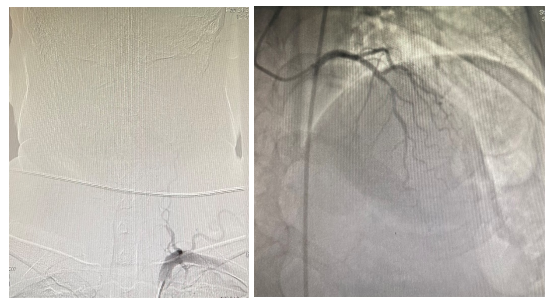

介入血管外科联合心血管内科完成我院首例同期全脑血管及冠脉造影术

日前,介入血管外科联合心血管内科,为同时患有心脑血管疾病的患者完成了同期全脑血管及冠脉造影术。 最近半年来张先生出现间断性头晕,近1个月来发作次数愈加频繁,且合并出现面部和肢体麻木。春节前,张先生来到了...